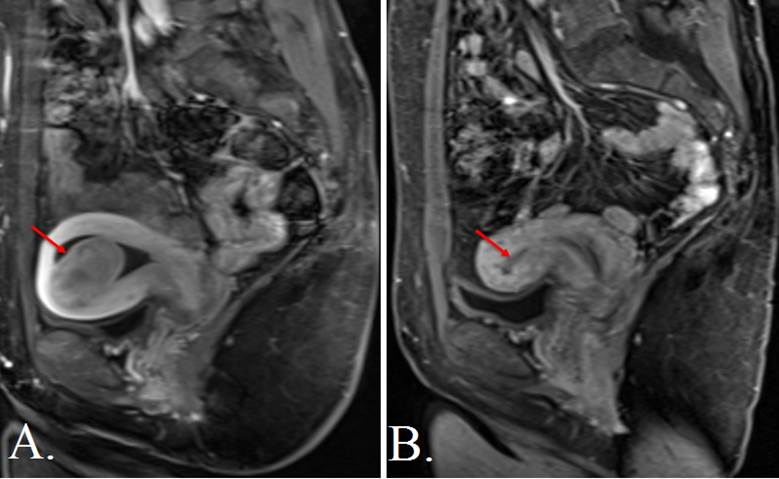

The radiologist uses imaging to guide a small catheter (thin tube) into the arteries supplying the fibroids with blood. The radiologist then releases small particles called microspheres, blocking the targeted arteries and depriving them of blood. The fibroids and the uterus then decrease in size.